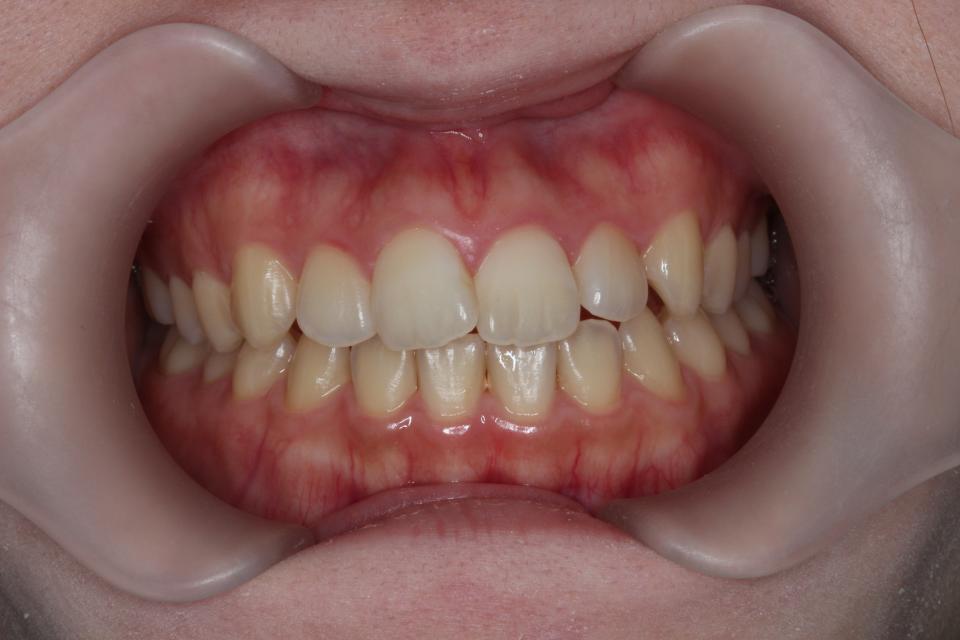

矯正治療前

20代女性の患者さんです。

上下の真ん中がズレているを気にして来院されました。